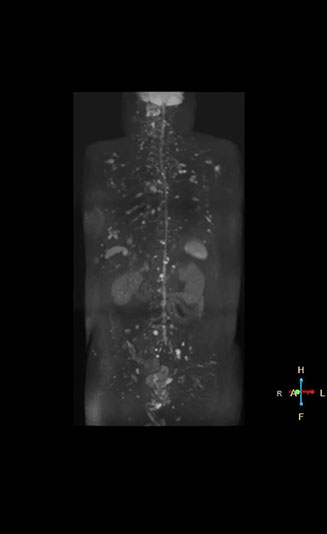

“Switching to coronal DWIBS – rather than axial – further shortens scan time,” says Mr. Naka. “Important is that a dS SENSE factor of 5 shortens exam time while high image quality can be maintained, thanks to Ingenia’s dStream architecture.” He adds that the coronal orientation also avoids artifacts that are specific to combining axial images.

“When we use a coronal DWIBS acquisition, we can perform a full whole body examination, including other required sequences, within 30 minutes,” he says.

Dr. Nobusawa notes that acceptance of whole body DWI accelerated after the hospital installed the Ingenia 1.5T which allowed them to optimize the protocol to their needs. “The Philips system helped us promote the technique, because the DWIBS image quality was so high with Ingenia. It provides high quality in the coronal images, and a short acquisition time plus high SNR thanks to the dStream technology,” he says.